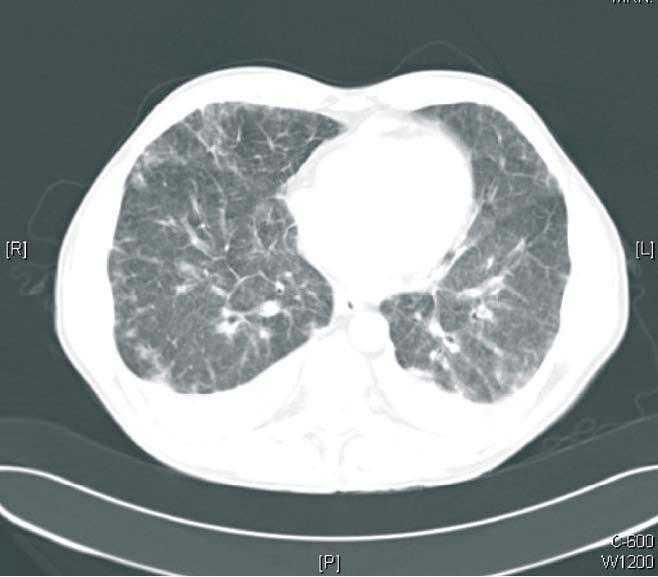

Laboratory findings were 3,980 WBC/µl (eosinophils 29.3%), haemoglobin 12.1 g/dl, platelets 276,000, creatinine 1.79 mg/dl, plasma sodium 138 mEq/l, plasma potassium 3.9 mE/l, and plasma levels of everolimus of 14 ng/ml. On the chest X-ray a bilateral interstitial pattern was seen and the chest CT showed pulmonary nodules and infiltrates with thickening of the bilateral interstitium (Figures 1 and 2). Antigen studies and cultures of cytomegalovirus (CMV) were negative, as also pneumococcal and Legionella antigen studies. A bronchoscopy was performed and signs of chronic bronchopathy were seen with negative BAl and BAS. Empiric treatment with wide spectrum antibiotics and antivirals was begun, without any clinical improvement and with radiological worsening. Therefore, suspecting pneumonitis due to everolimus, we decided to discontinue this drug and introduce tacrolimus. On the day after discontinuing everolimus the patient presented clinical and radiological improvement with resolution of the condition.

Figure 2. Chest CT